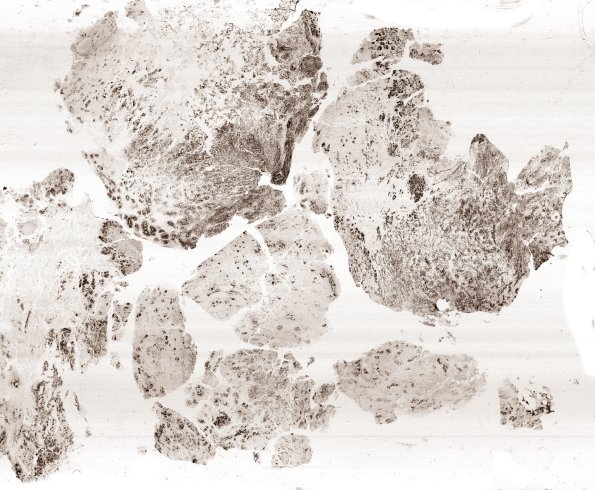

Washington University Experience | NEOPLASMS (EMBRYONAL) | ETMR - Embryonal Tumor Multilayered Rosettes | 8G1 ETMR (Case 8) Ki67 B1 WM

Tumor in this whole mount exhibits an estimated Ki-67/MiB proliferative index exceeding 80% in the most cellular foci. (Ki67 IHC)